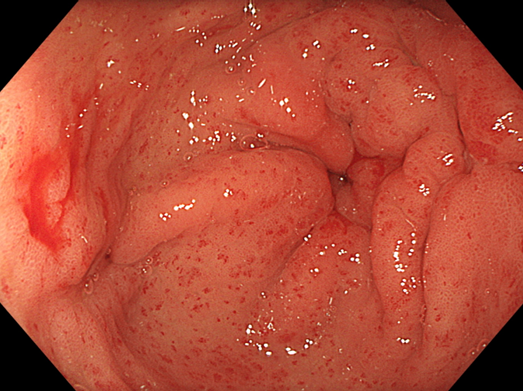

Hang vị dạ dày xuất hiện các vệt giãn mạch máu đỏ, hình ảnh đặc trưng của hội chứng “dạ dày dưa hấu”

Trong quá trình cấp cứu này, BS.CKI Nguyễn Lâm Vĩnh Phúc - Phó trưởng Khoa Nội tổng hợp, Bệnh viện Đa khoa Quốc tế Nam Sài Gòn, phát hiện niêm mạc dạ dày người bệnh xuất hiện các vệt mạch máu giãn đỏ rực, hội tụ về phía môn vị, giống như những sọc trên vỏ quả dưa hấu - hình ảnh điển hình của hội chứng GAVE (Gastric Antral Vascular Ectasia), hay còn gọi là "dạ dày dưa hấu".

Giải thích về căn bệnh này, BS.CKI Nguyễn Lâm Vĩnh Phúc cho biết: "Hội chứng GAVE (Gastric Antral Vascular Ectasia) là tình trạng giãn mạch máu bất thường tại vùng hang vị dạ dày. Tên gọi "dạ dày dưa hấu" bắt nguồn từ hình ảnh nội soi đặc trưng của bệnh, khi các mạch máu giãn đỏ tạo thành những dải chạy dọc trên niêm mạc dạ dày, nhìn giống các sọc trên vỏ quả dưa hấu".